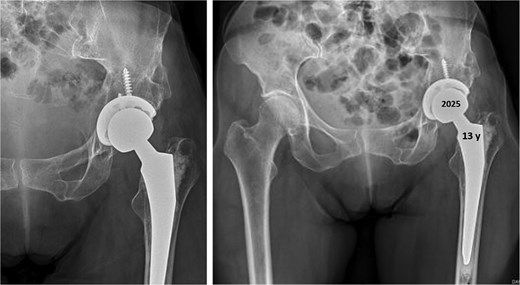

Thirteen years after THA, the 76-year-old patient continued to have a stable asymptomatic hip. Hip radiographs showed unchanged and stable positioning of the acetabular cup and femoral stem, with no measurable subsidence or radiolucent lines around the components (Fig. 4).

Postoperative anteroposterior radiographs of the pelvis 13 years after the THA, showing mechanical stability of the prosthesis with no evidence of loosening. No signs of osteoarthritis are present in the right hip (Tönnis Grade 0).

Thirteen years after the arthroplasty surgery, the 76-year-old patient presented an asymptomatic hip. The hip radiographs showed a satisfactory orientation of the prosthesis and no signs of mechanical instability or radiolucent lines around the prosthesis.